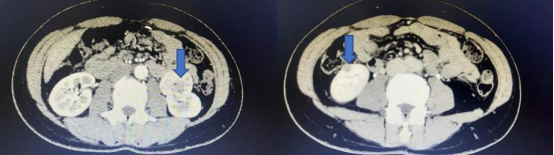

今年48岁的齐女士因体检发现左肾长了一个4公分大小的肿瘤,住院后为进一步明确诊断,完善肾脏增强CT,结果意外发现右肾也存在一个大小约1公分的肿瘤,王女士得知后决定完善全身PET-CT检查,PET-CT提示双肾病变,未见转移。王春阳告诉患者家属目前患者双肾肿瘤还没有转移,尽快手术是最好的治疗方案。为完整切除双侧肾肿瘤,并且最大限度保留肾脏功能,同时实现微创效果,在患者及家属积极要求下,王春阳团队决定为患者行机器人辅助腹腔镜下双肾肿瘤切除术。